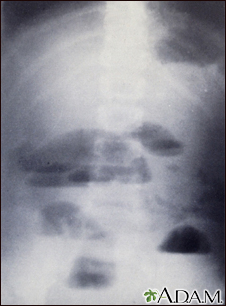

Small bowel obstruction - x-rayBackSmall bowel obstruction - x-rayX-rays of the abdomen are important in diagnosing the presence of small bowel obstruction. When obstruction occurs, both fluid and gas collect in the intestine. They produce a characteristic pattern called "air-fluid levels". The air rises above the fluid and there is a flat surface at the "air-fluid" interface. E-mail FormEmail ResultsName:Email address:Recipients Name:Recipients address:Message: